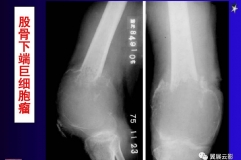

健康科普:如何判斷骨腫瘤?

健康科普:如何判斷骨腫瘤?  一般而言,體表的軟組織腫瘤比較好發(fā)現(xiàn),但是被豐富的肌肉組織等包圍的骨骼病變在早期則不容易被發(fā)現(xiàn),所以專家提倡早發(fā)現(xiàn)、早治療。

健康科普:骨腫瘤是什么?

健康科普:骨腫瘤是什么? 骨腫瘤是一類疾病的總稱,包括原發(fā)的腫瘤和轉(zhuǎn)移來的繼發(fā)性腫瘤兩大類。